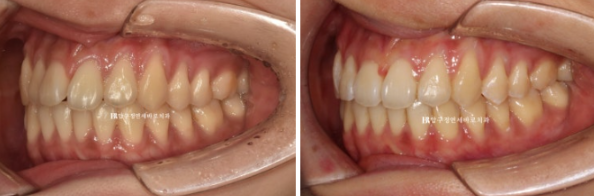

치료 전 - 치료 후 비교 사진입니다.

초진 24.02 이며 치료 종료는 24.07입니다.

24.02~24.07

토끼이빨은 정상 배열을 찾앗습니다.

깔끔해진 미소를 가지게 되었습니다.